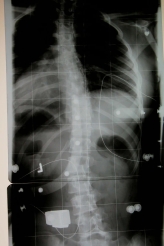

ich finde Denises Röntgenbild bemerkenswert.

Die meisten Skoliosen haben einen oder zwei Hauptbögen, hier sehe ich aber drei Hauptbögen, d.h. nach der Schrothschen Einteilung wäre die Skoliose nicht drei-, nicht vier-, sondern fünfbogig!

Ich fände jetzt den Ausgangsbefund sehr interessant zum Vergleich, d.h.: wieviel Prozent beträgt die Korrektur, und: ist vielleicht einer der Bögen erst durch das Korsett entstanden?!

Ich finde auch, dass Denises Korsett merkwürdig wirkt. Sie steht überhaupt nicht im Lot, und das typische Cheneau-Prinzip, alle Druckpunkte mit gegenüberliegenden Freiräumen zu kombinieren, scheint hier nicht wirklich angewendet zu sein.

Aber wie gesagt, finde ich das ganze ohne Vergleich mit dem Ausgangswert und dem weiteren Verlauf schwierig zu beurteilen.